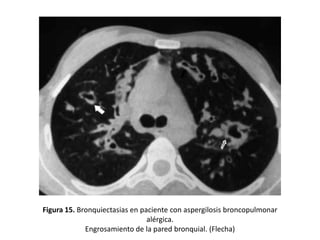

Signos indirectos

• Engrosamiento de la pared bronquial:

– Mayor de 50% del diámetro de la arteria adyacente.

– Es un hallazgo muy frecuente pero inespecífico ya que puede aparecer

en otras patologías.

– Se debe medir mediante el índice de luz bronquial, que es el cociente

entre el diámetro interno y externo del bronquio (Figura 15).

Figura 15. Bronquiectasias en paciente con aspergilosis broncopulmonar

alérgica.

Engrosamiento de la pared bronquial. (Flecha)